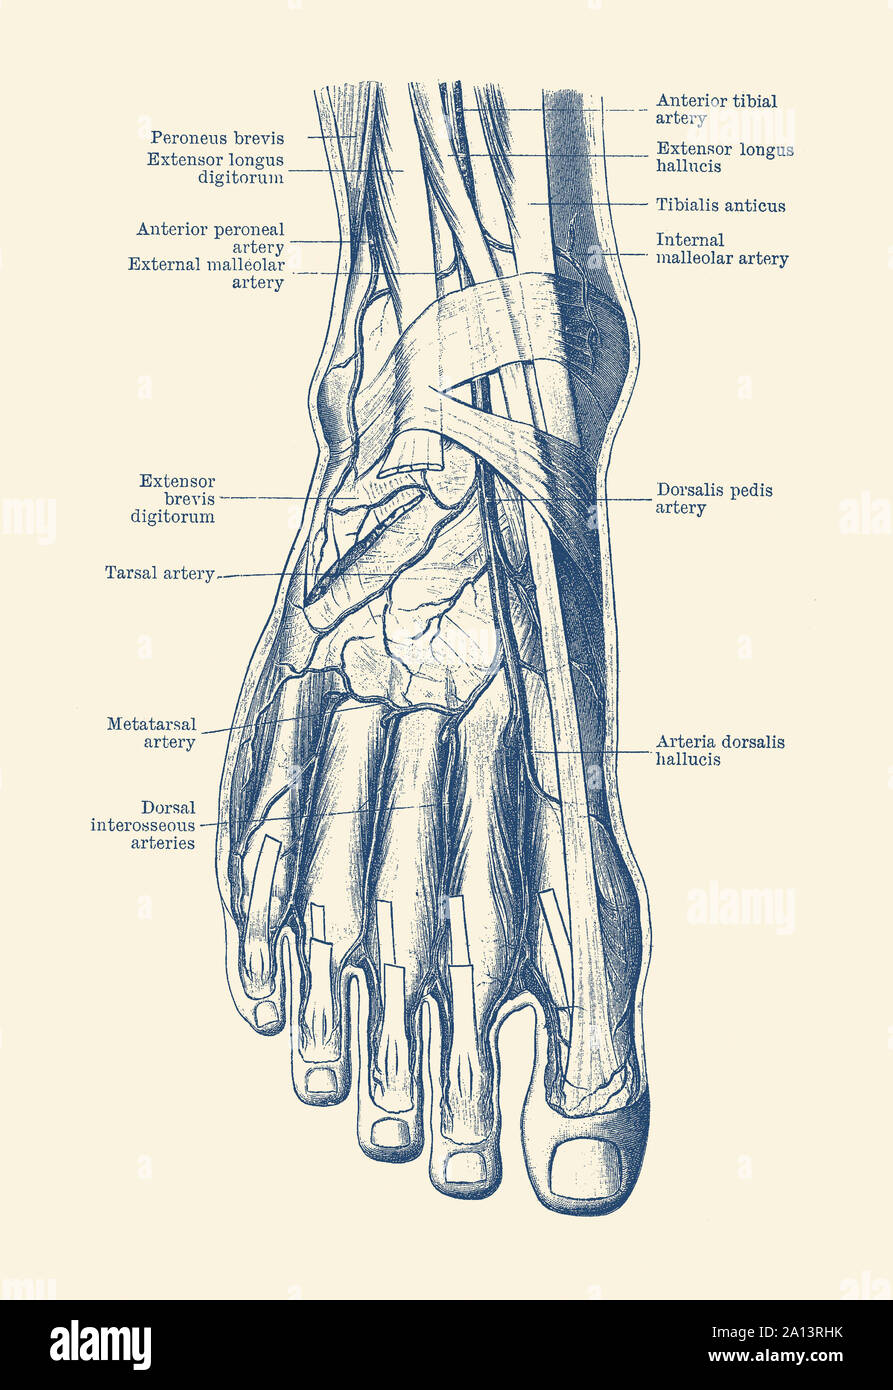

RF2ABM669–La médecine et les soins de l'illustre le tableau, les droits de l'anatomie du pied : Peau et tissus ectodermaux, os, muscles nerfs, vaisseaux sanguins